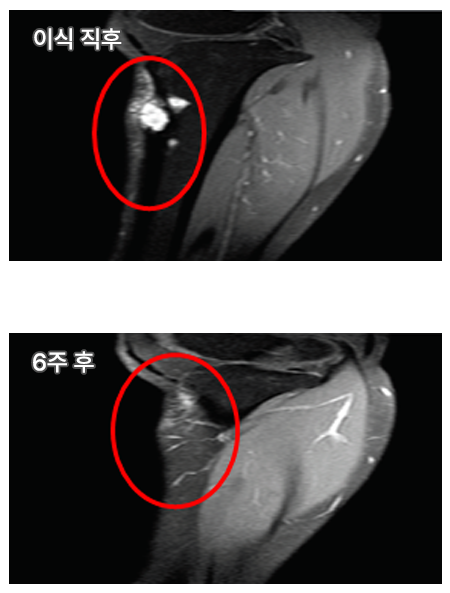

NEO BONE 임상실험 결과

임상실험 결과, NEO BONE은 빠른 초기 골유합과 이상적인 생분해성으로 1년 이후 골정상화 및 신생골 형성에 탁월함 을 나타냈습니다.